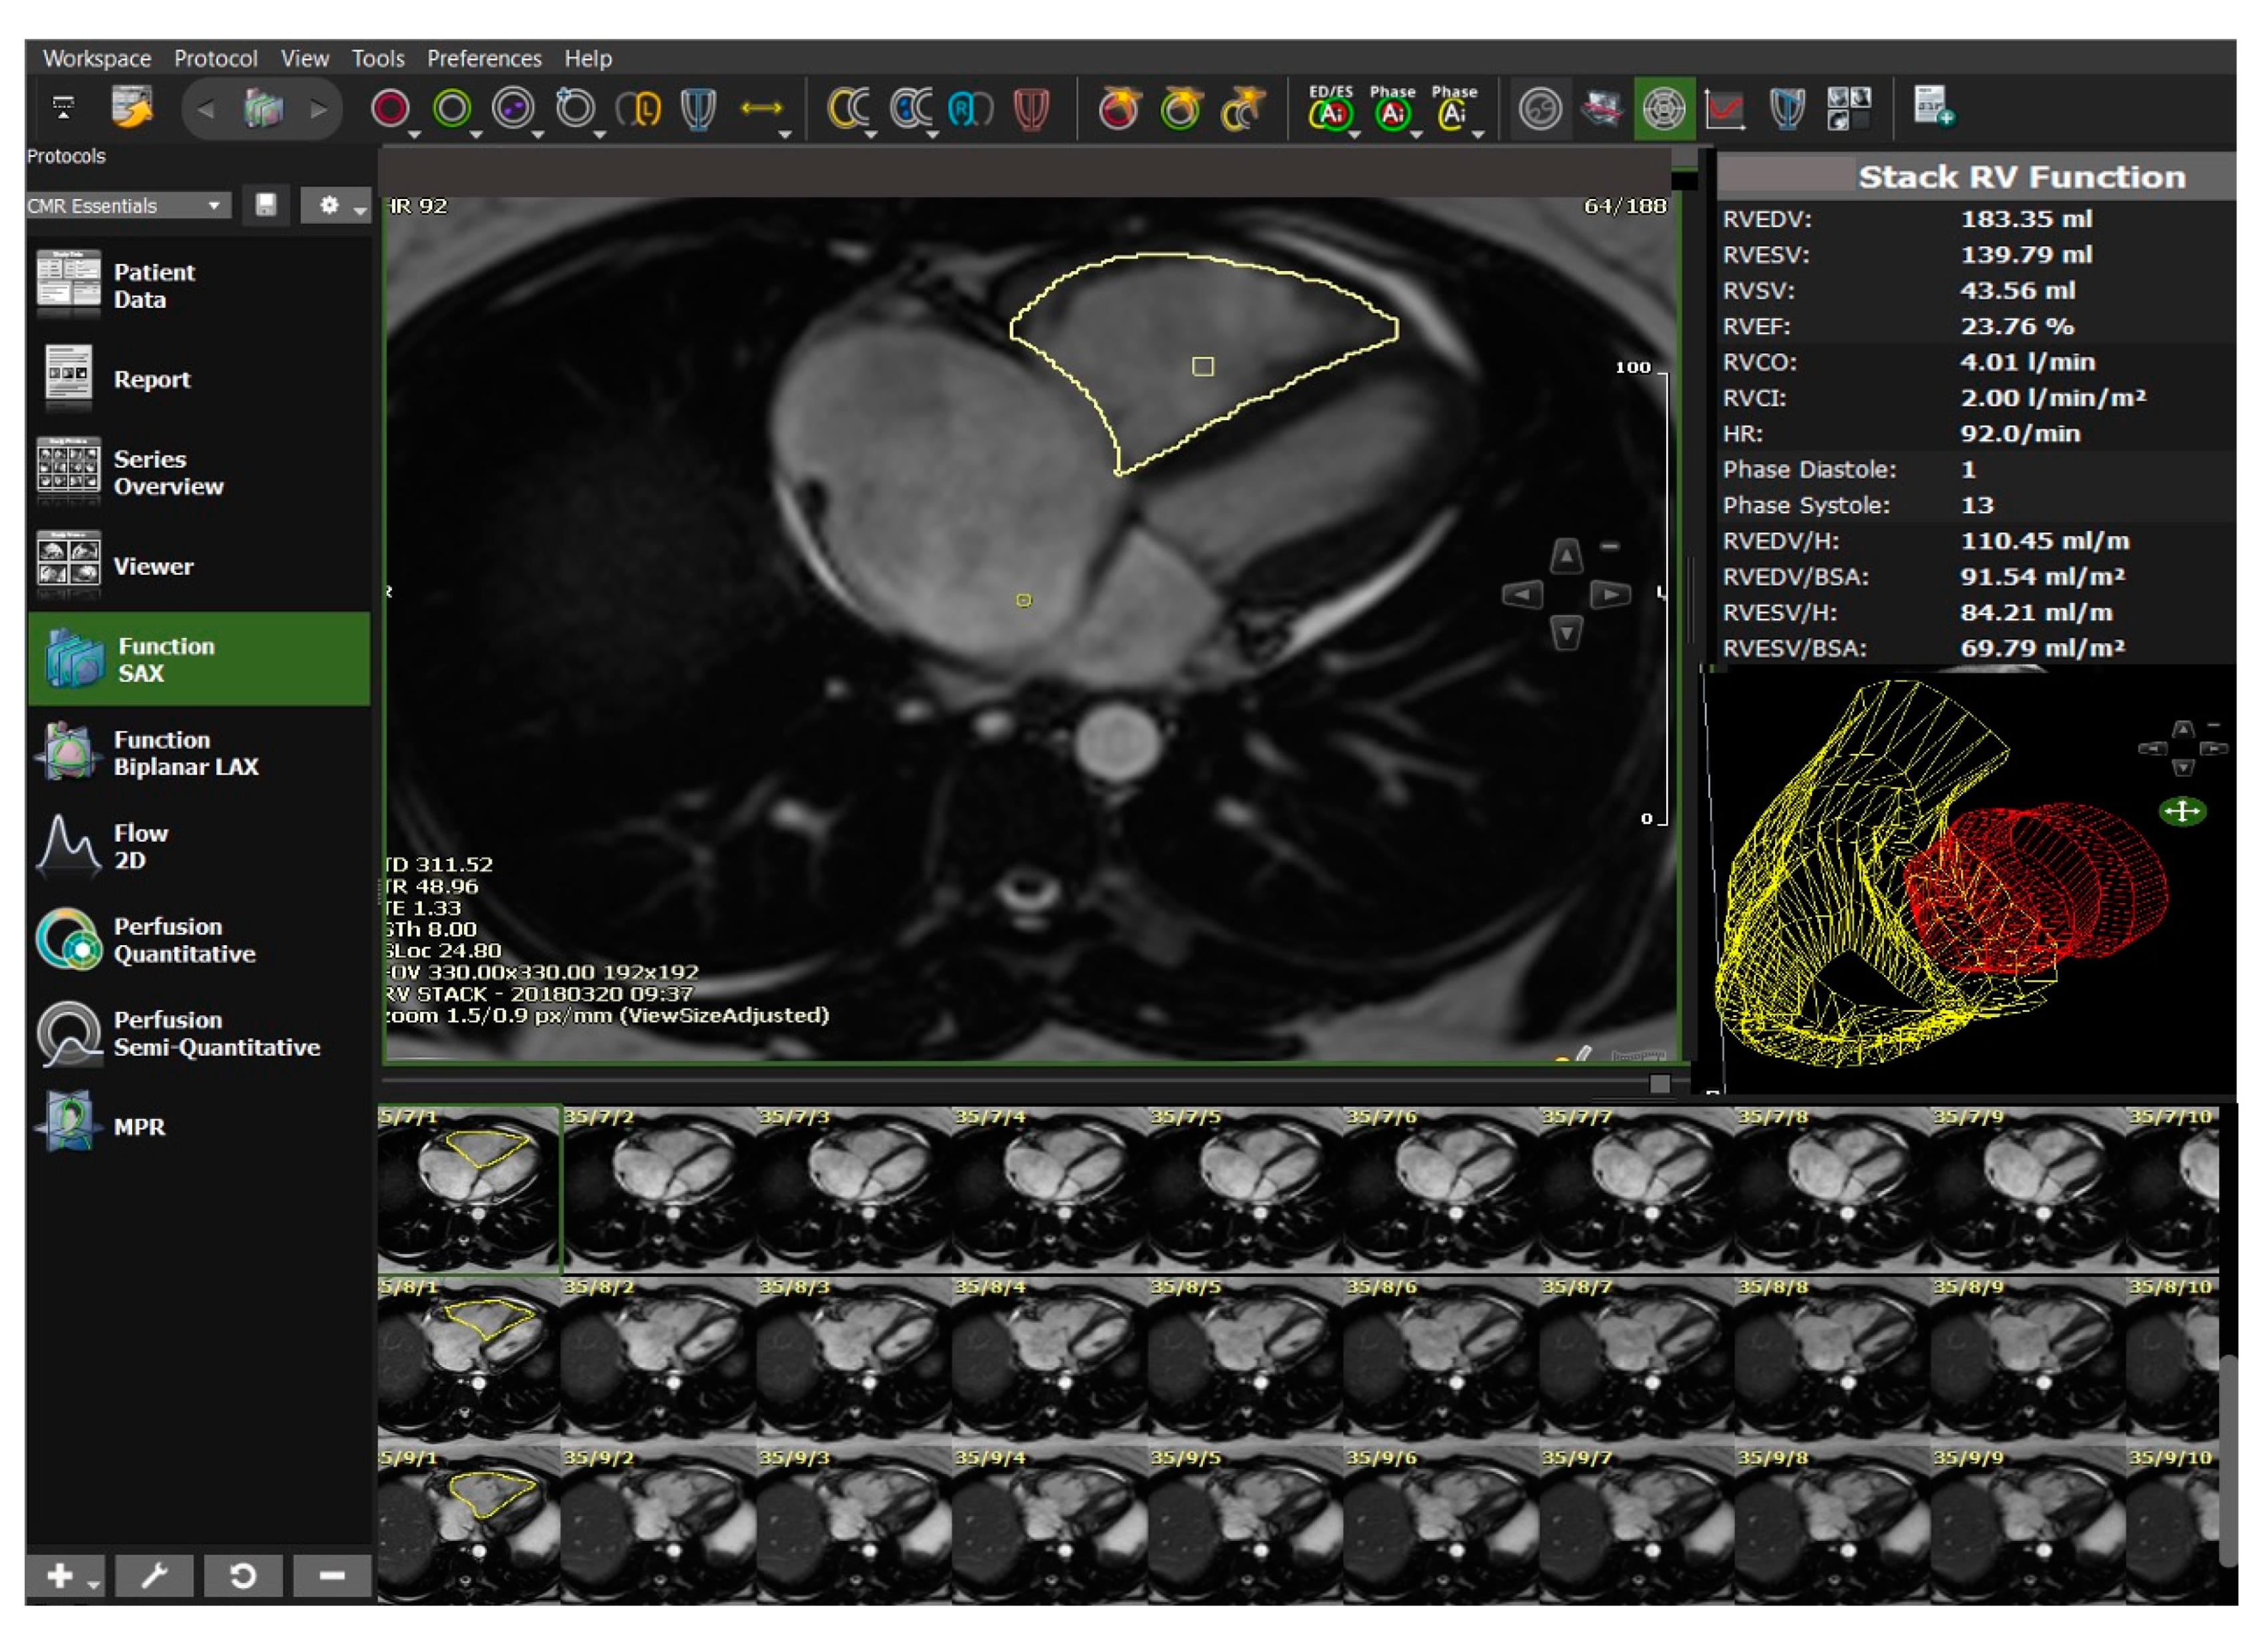

5.4. Cardiovascular Magnetic Resonance (CMR)